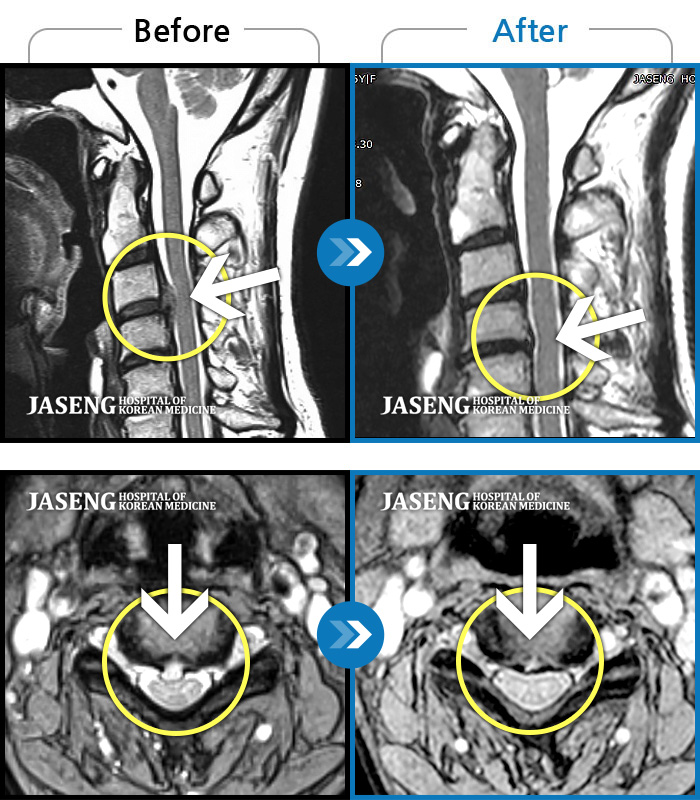

MRI 치료사례

양측 승모근 통증과 목 통증, 견갑골 통증으로 고개를 돌릴때 통증을 호소하는 환자였습니다.